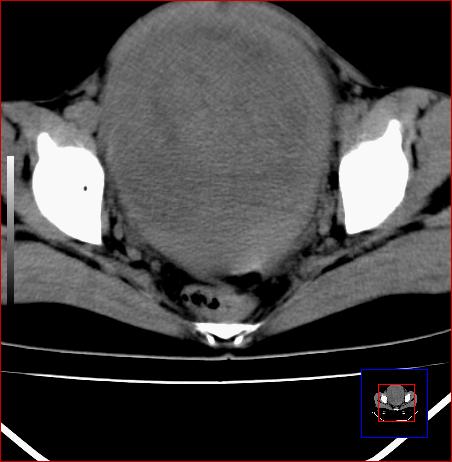

标题: CT15141:子宫肌瘤还是卵巢肿瘤 [打印本页]

标题: CT15141:子宫肌瘤还是卵巢肿瘤

腹部包块1年余,近两月明显增大,月经量多

病灶呈实性包块,边界清晰,似与子宫分界不清,考虑:子宫肌瘤

子宫体积增大,内密度不均匀。边缘清晰。考虑子宫肌瘤。